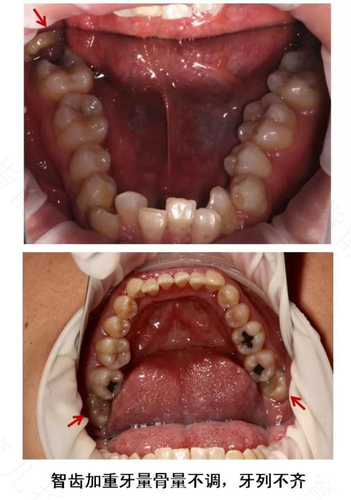

只有当智齿出现严重蛀牙、导致邻牙病变、引发炎症(如牙髓炎、冠周炎等)、智齿阻生以及智齿长出后有不明原因的牙痛等情况,经过咨询医生之后,是可以将智齿拔掉,将因智齿造成的问题能够一次性解决,如果想要拔除智齿,一定要到正规口腔医院就医诊治。